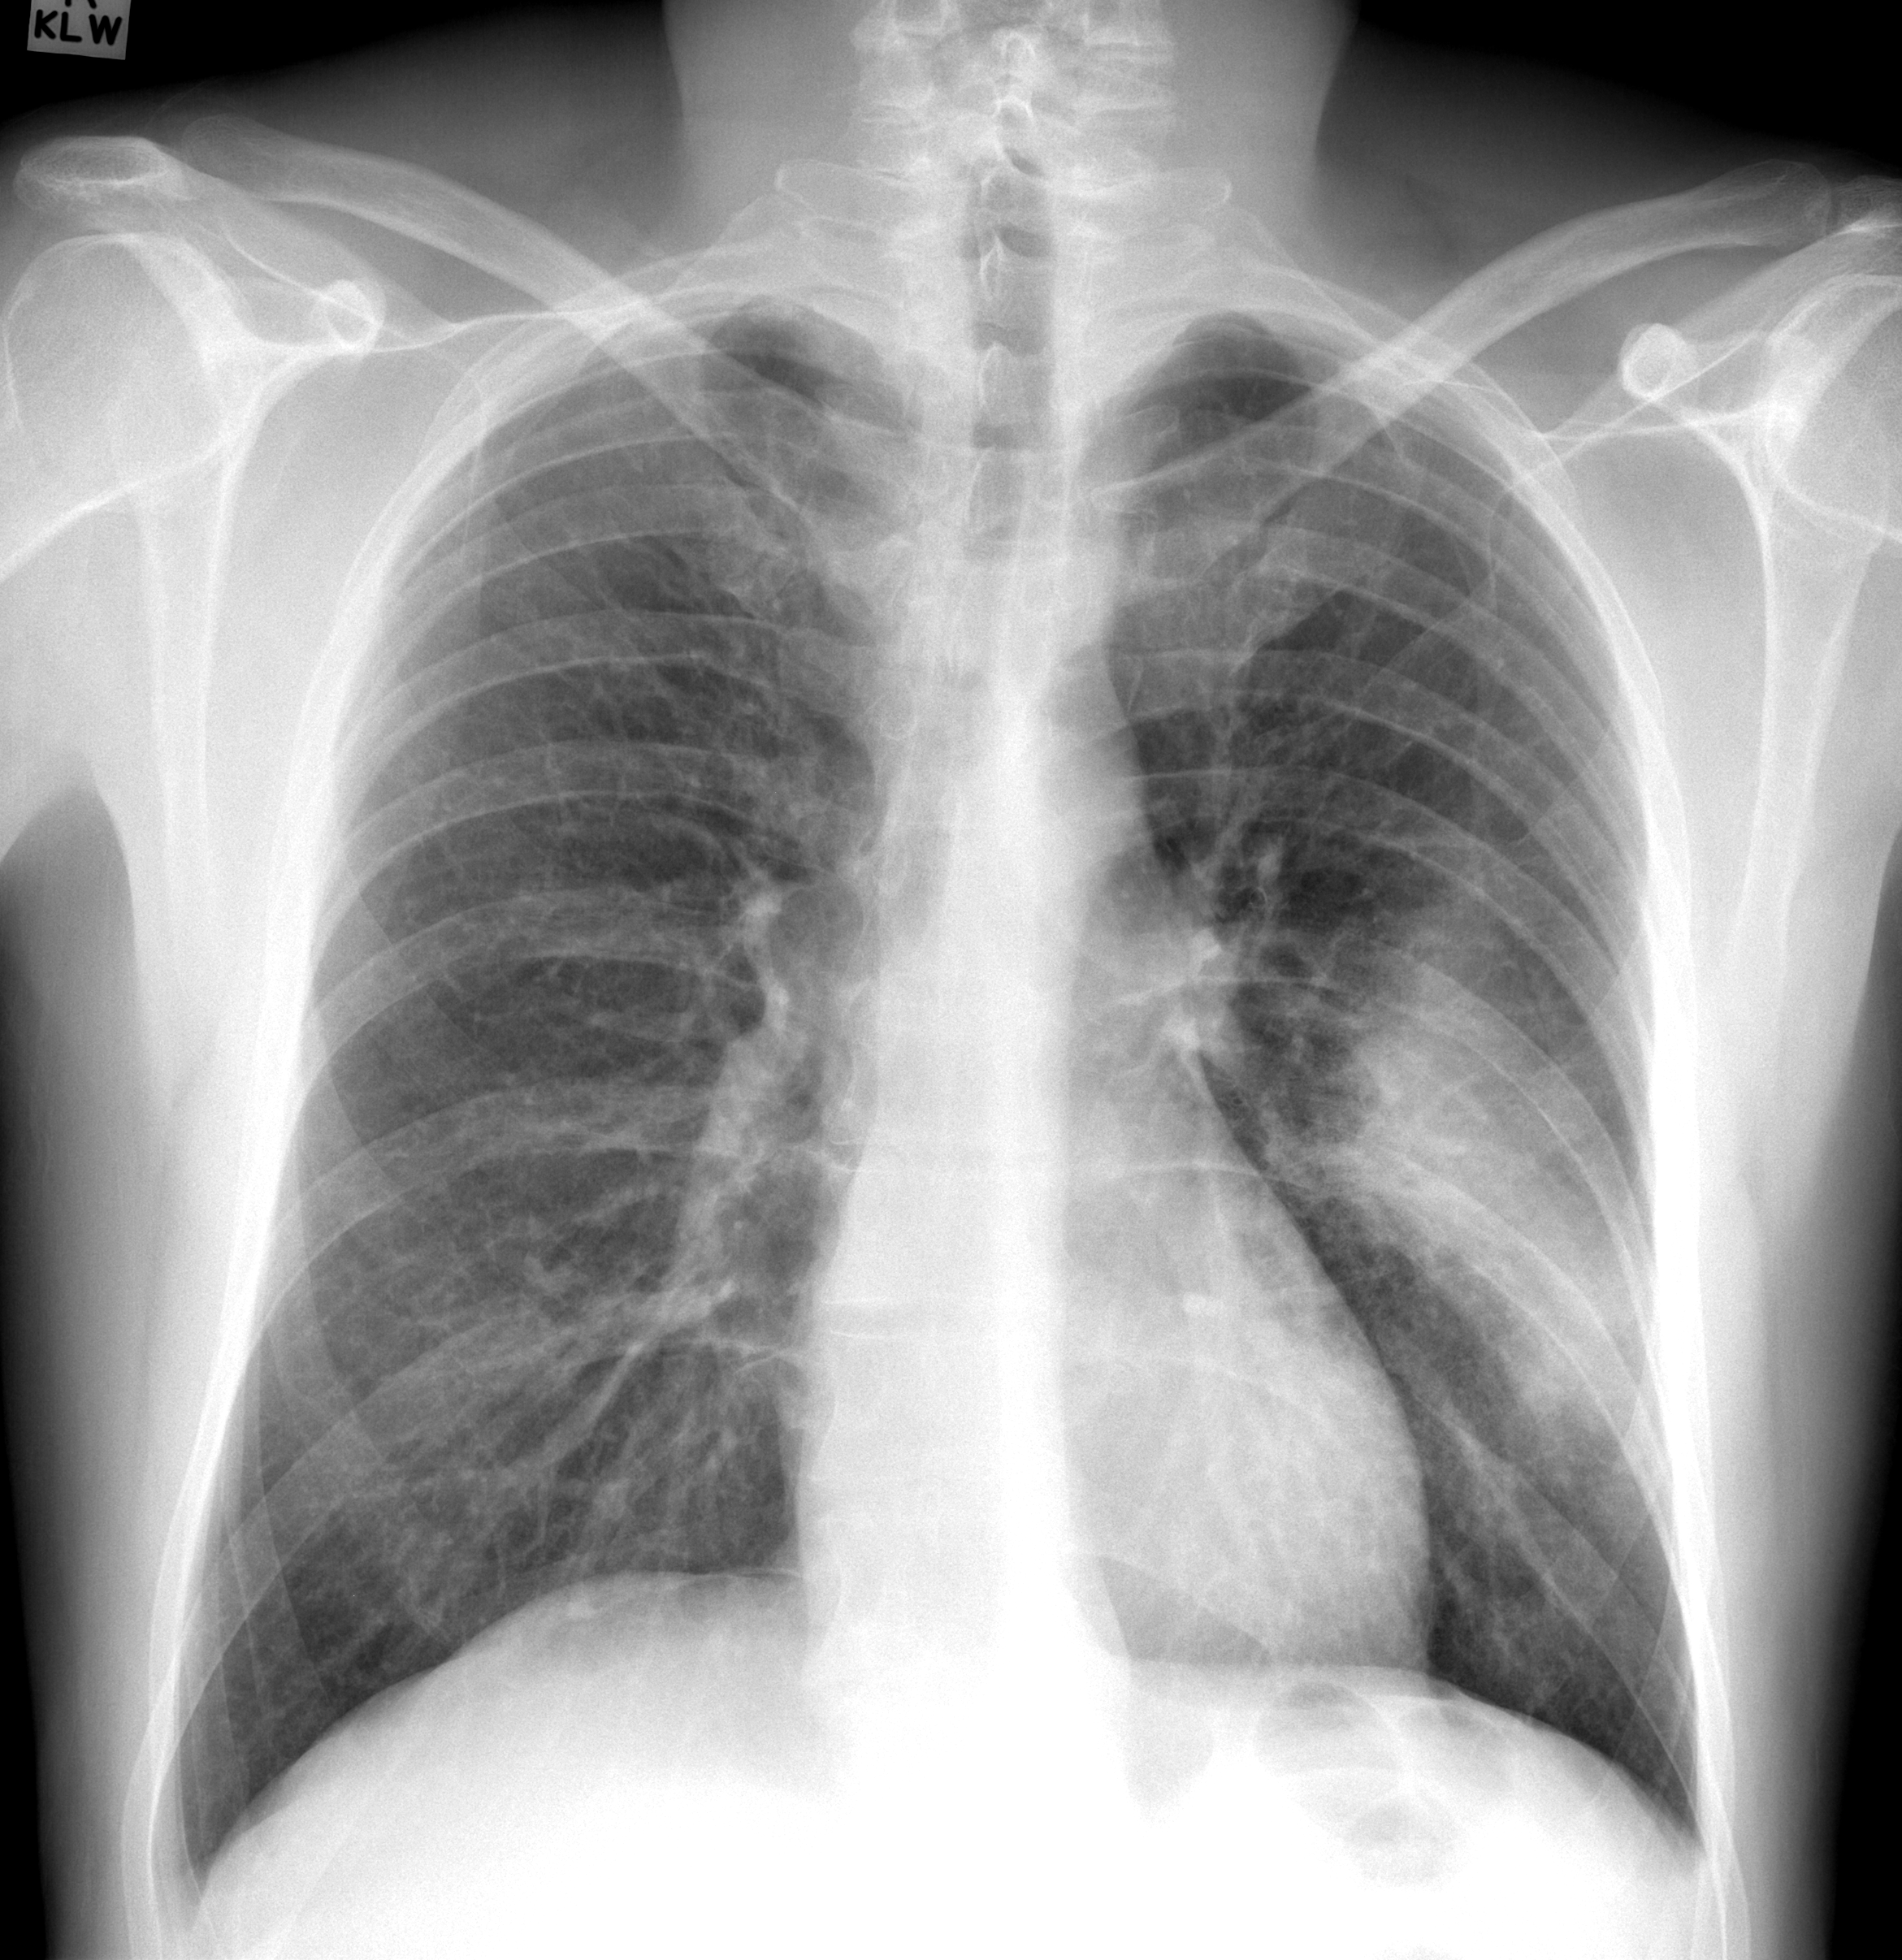

(a) Lungs of a healthy patient.

Figure 1: Examples of PA chest X-rays in the data-set in Figures 1(a) to 1(d), and distribution of the diagnoses based on the PA chest X-rays in Figure 1(e).